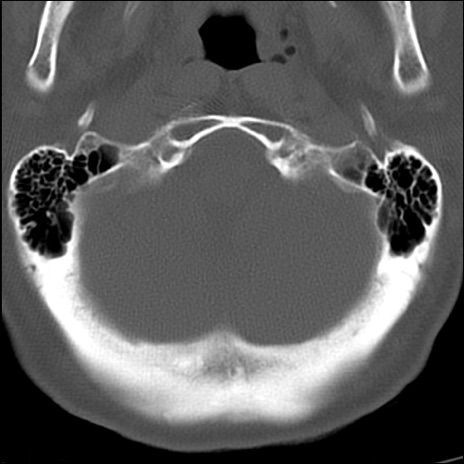

症例48 頚椎CT(横断像)

頚椎CT